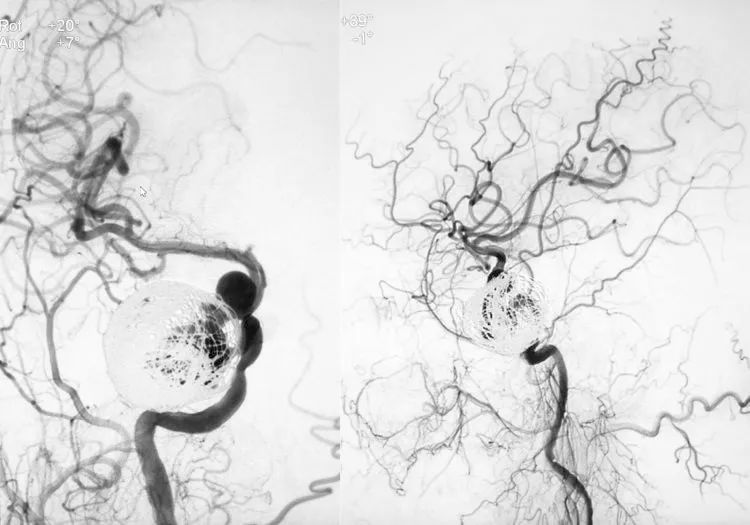

术后右颈内动脉各角度造影显示大瘤部分栓塞,载瘤动脉畅通,希望通过一段时间的血流冲击使大瘤内的弹簧圈夯实,为二期支架导管的通过提供铺垫和支撑。

1个半月后二期行密网支架置入。

5F Navien中间导管置入右颈内动脉岩骨段,行右颈内动脉造影显示大瘤大部栓塞,瘤颈处开放。